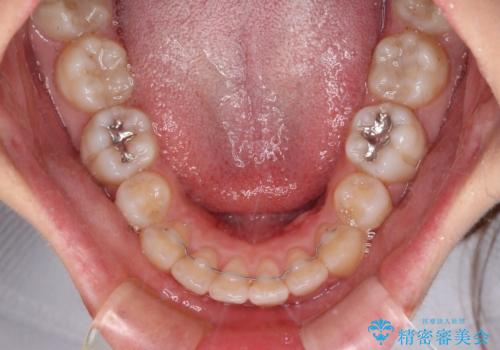

- 下顎前歯を中心に、以前行った矯正治療の後戻りが気になるとのことで来院された患者様です。

後戻りは軽度であったため、インビザライン・ライトにて治療を行うこととしました。

治療途中で出産をされたため、通院が困難となりましたが、インビザライン・ライトでの治療可能期限である2年以内に無事に治療を終えることができました。